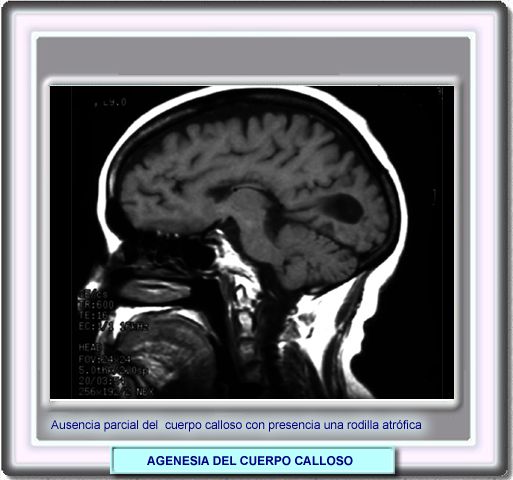

AGENESIA DEL CUERPO CALLOSO